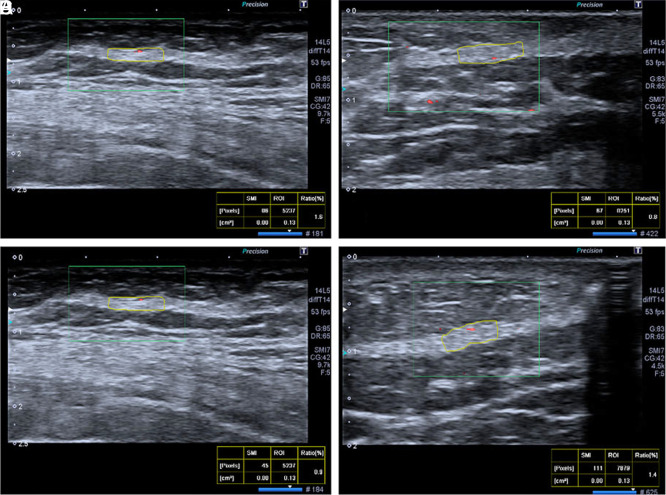

Objective: Superb microvascular imaging is a Doppler technique that increases the visibility of small vessels and gives quantitative information about tissue blood supply by measuring the vascular index. In this study, it is aimed to evaluate the long-term and postradiotherapy changes in blood flow of buried de-epitelized flaps in breast reconstruction by using the quantitative values obtained through superb microvascular imaging.

Materials and methods: Retrospective review of the 14 patients who underwent nipple-sparing breastconserving surgery and immediately breast reconstruction with a de-epitelized extended latissimus dorsi flap was done. In order to demonstrate the effect of radiotherapy on flaps microvascular circulation, patients were evaluated using superb microvascular imaging postoperative first week, first month, and postradiotherapy first week and sixth month. The normal distribution of the data was evaluated with the Shapiro-Wilk test. Paired samples t-test was used for comparisons.

Results: According to the paired samples t-tests, postoperative first week mean vascular index was higher than postoperative first month and postradiotherapy first week (P < .05). Besides, postradiotherapy first week mean vascular index was higher than postoperative first month and also than postradiotherapy sixth month (P < .05).

Conclusion: Radiotherapy can affect the results of breast reconstruction by endothelial and fibrotic injury. In this study, the changes in the microvascular circulation of the latissimus dorsi flap were discussed and found to increase at postoperative and postradiotherapy early period related to inflammation and not decreased significantly at long-term follow-up after radiotherapy.